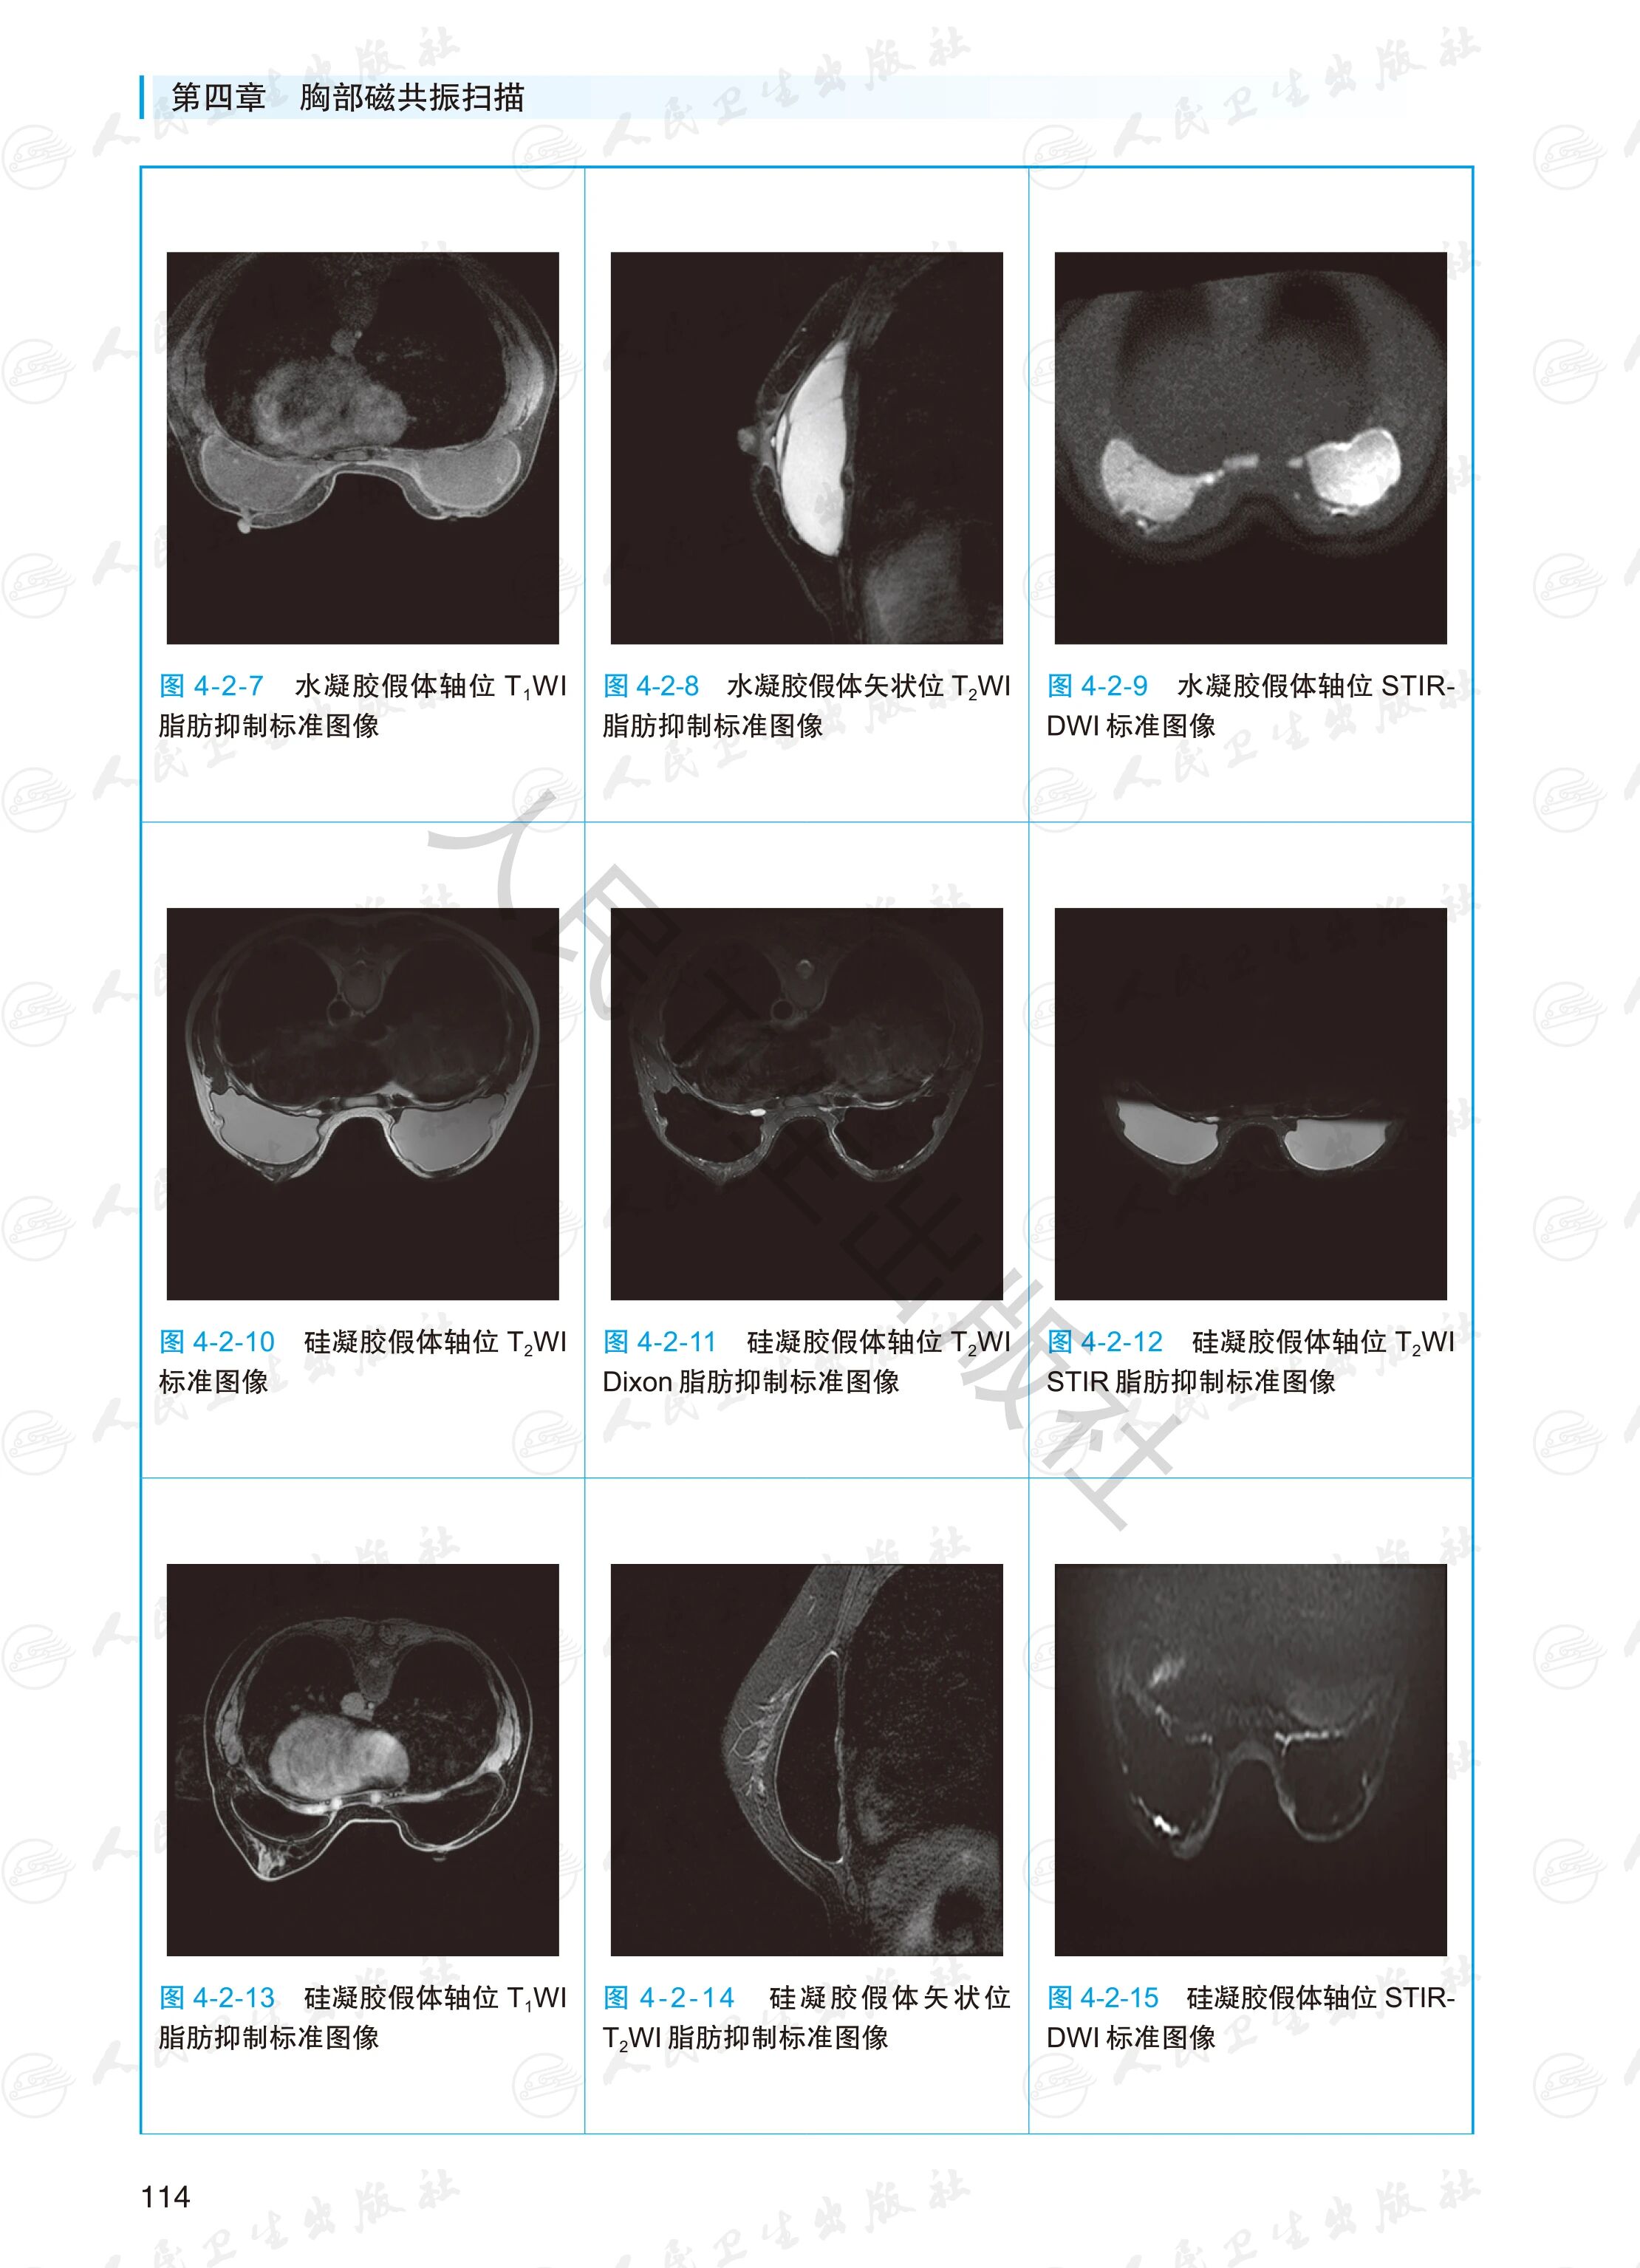

涵盖全身各部位MR检查项目,每个检查项目包括患者准备和摆位、扫描序列、扫描定位、参数要求、质量要求、标准图像示例、伪影图像、特殊注意事项等。